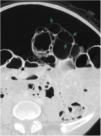

A previously healthy 65-year-old woman presented with symptoms of colicky abdominal pain and intense bloating, nausea and vomiting, and 8kg weight loss within the past 12 months. Her vital signs were stable, and she had no signs of peritoneal irritation. Abdominal angiotomography identified diffuse pneumatosis intestinalis with a predominantly cystic pattern, as well as abundant intraperitoneal free air, free fluid in the pelvic cavity, and no alterations in the mesenteric vasculature (figs. 1-3). Her laboratory test results ruled out gastrointestinal, infectious, oncologic, rheumatologic, pulmonary, and pharmacologic causes that would explain the tomographic findings. The patient received treatment based on metronidazole, probiotics, and prucalopride, and presented with partial symptom improvement, but no remission of the radiologic findings after 6 months of follow-up. The present case illustrates the fact that not all patients with pneumatosis intestinalis or pneumoperitoneum should be managed surgically. Pneumatosis cystoides intestinalis is a rare radiologic finding of unknown etiology. The differential diagnosis includes numerous causes, particularly intestinal ischemia. Treatment consists of antibiotics, prokinetics, hyperbaric oxygen, or endoscopic lesion resection, with varying results. Its clinical progression tends to be chronic and benign.